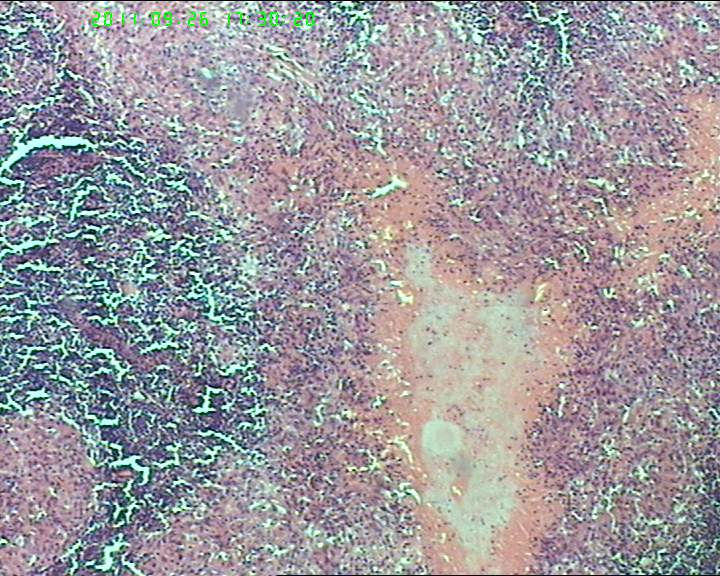

灰白不整形肿物一个,大小3.5*2.5*2cm,包膜完整。

21岁女性左侧颌下淋巴结,该诊断什么?图3

慢性肉芽肿性炎症,形态学倾向结节病,但是作为病理工作者对于这样的病例,再结合咋们国情,还是建议临床除外增殖性结核后再考虑结节病。

肉芽肿性炎,考虑结核不除外结节病